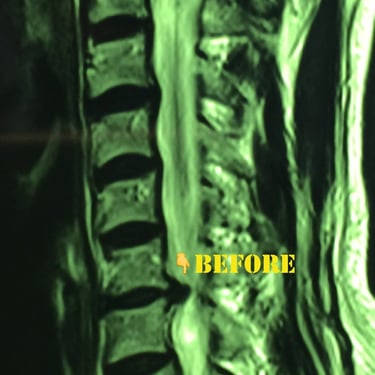

This young lady had a disc herniation at T12-L1 and was seeking treatment due to localized and radiating pain. In the images below:

The patient during the Discogel injection, the site of injection, immediate CT scans after Discogel injection, and a picture of the patient 8 years after Discogel injection. She is now a professional athlete, with her pain issues resolved